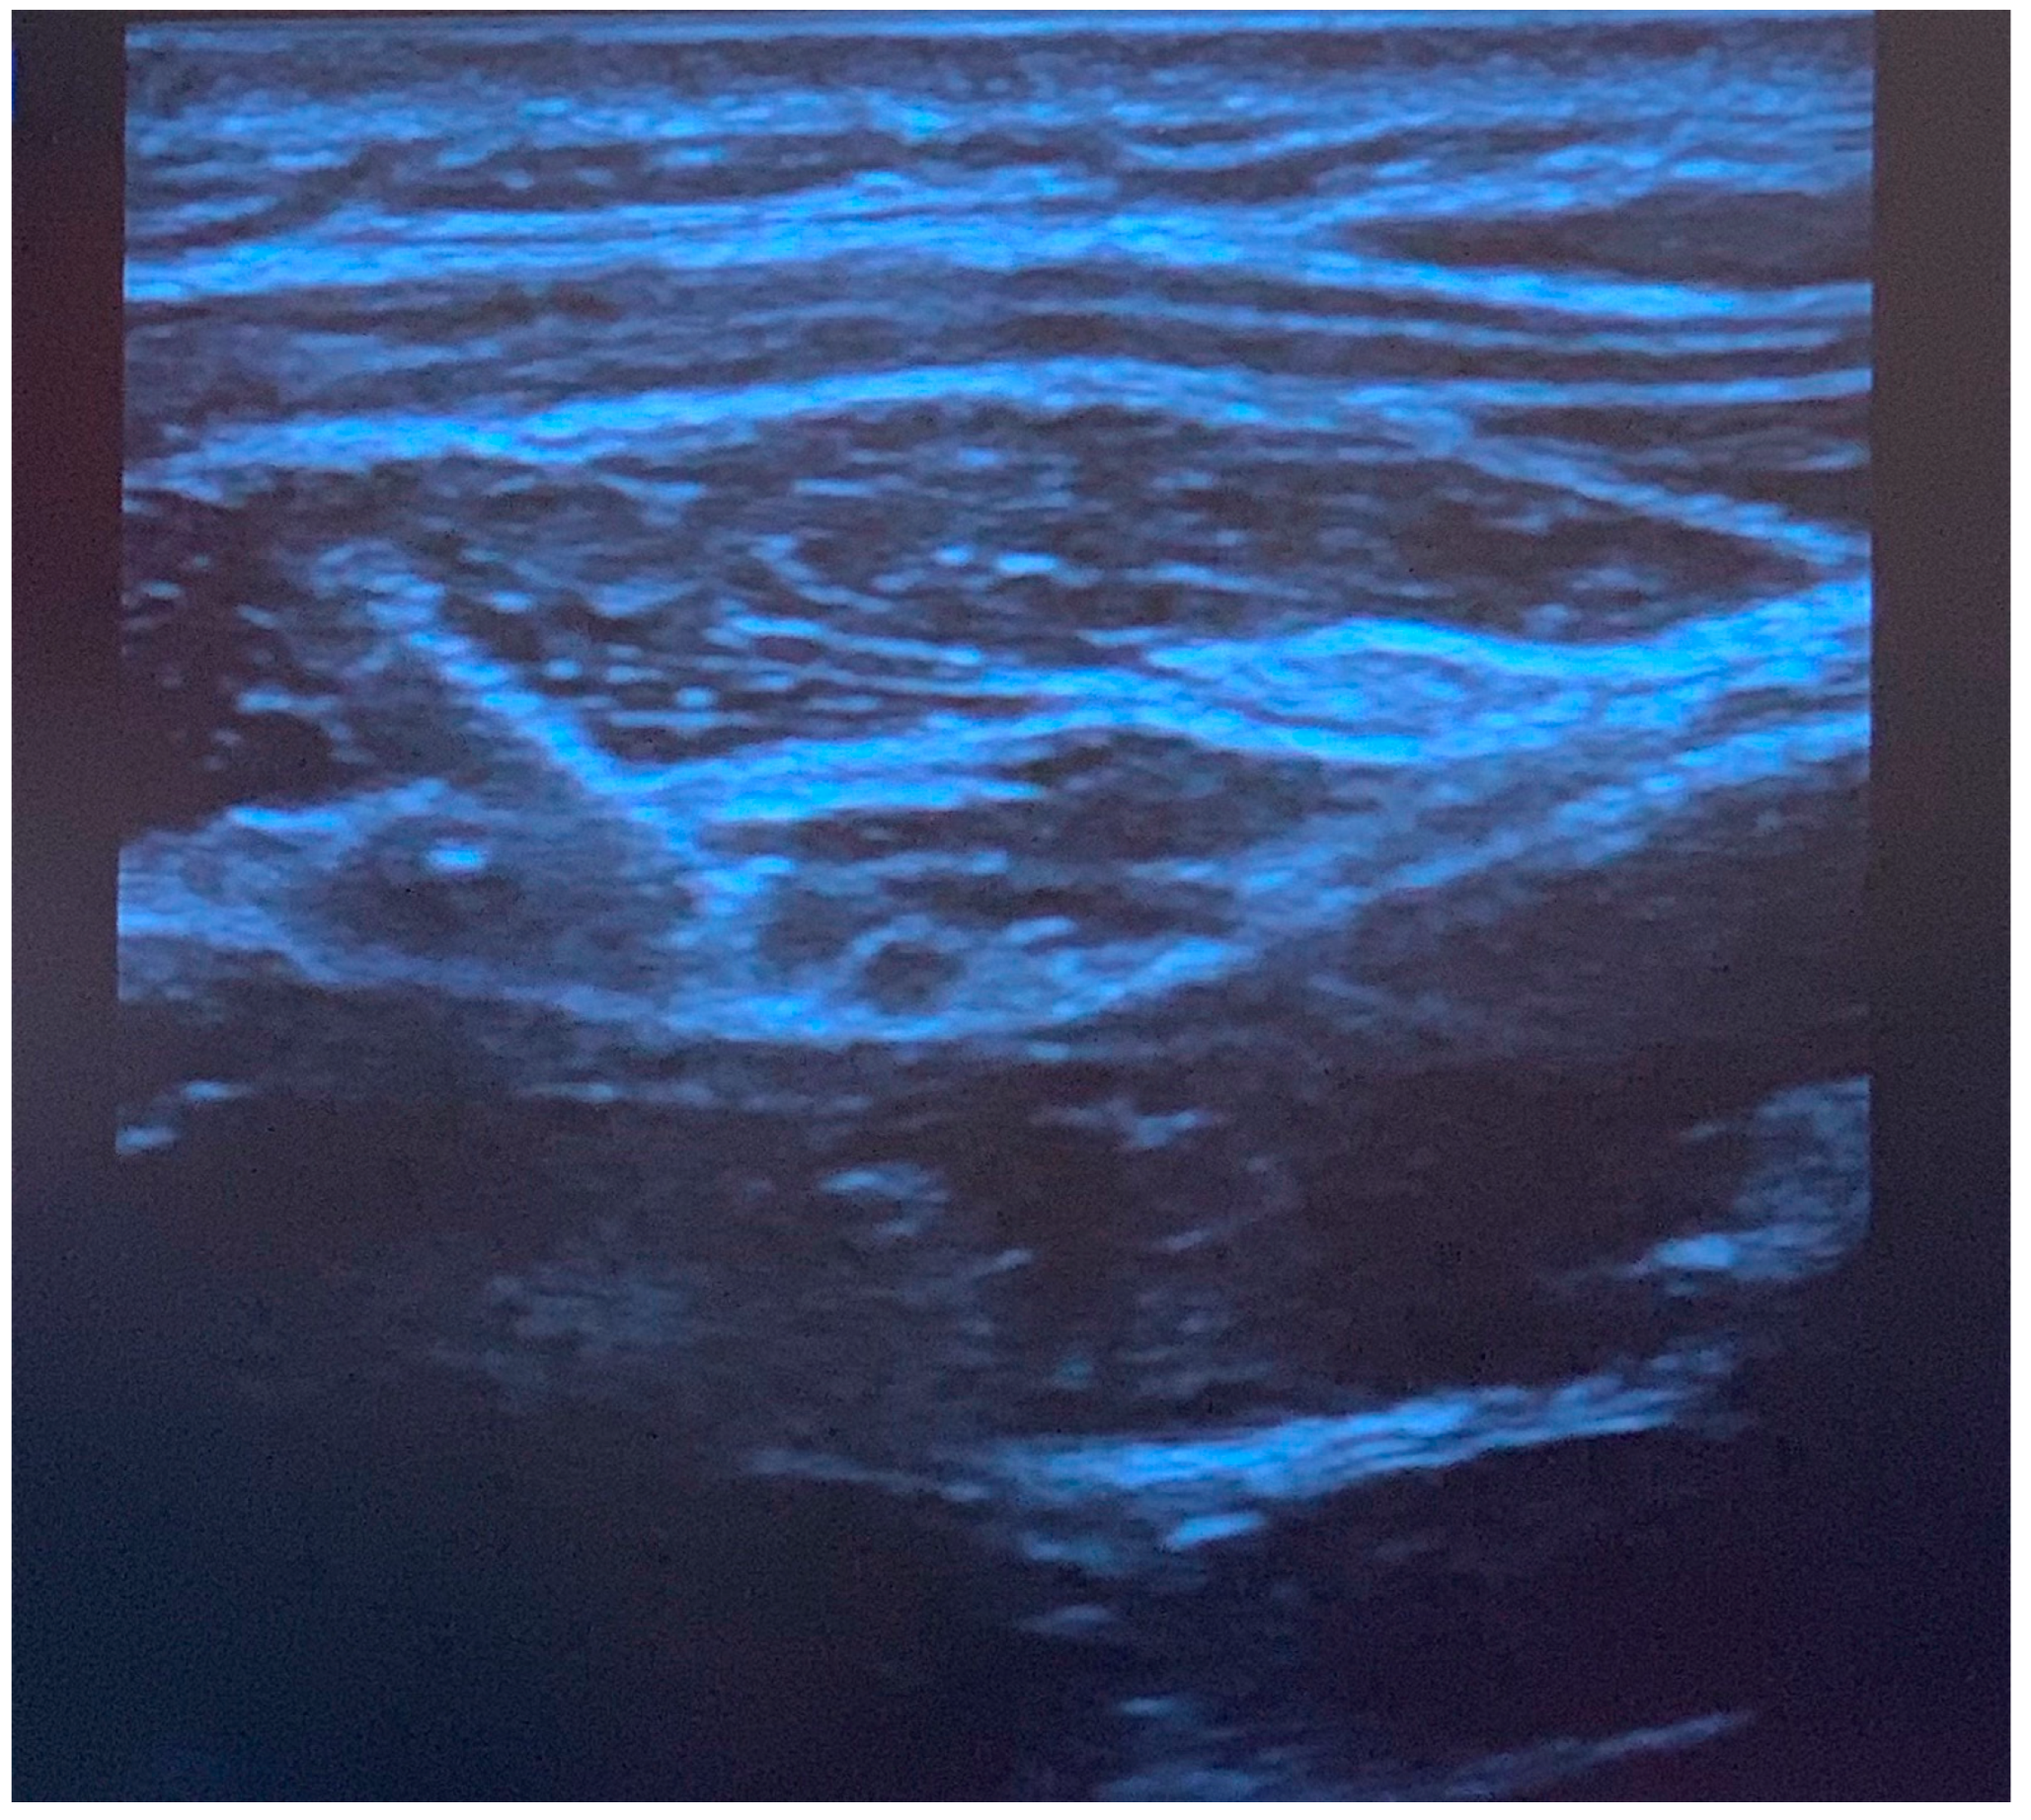

Figure 2.

Ultrasound image of greater occipital nerve block injection. The needle is positioned superior to the obliquus capitis inferior muscle, and local anesthetic spread is observed in the fascial plane. The semispinalis muscle is observed above the fascia.